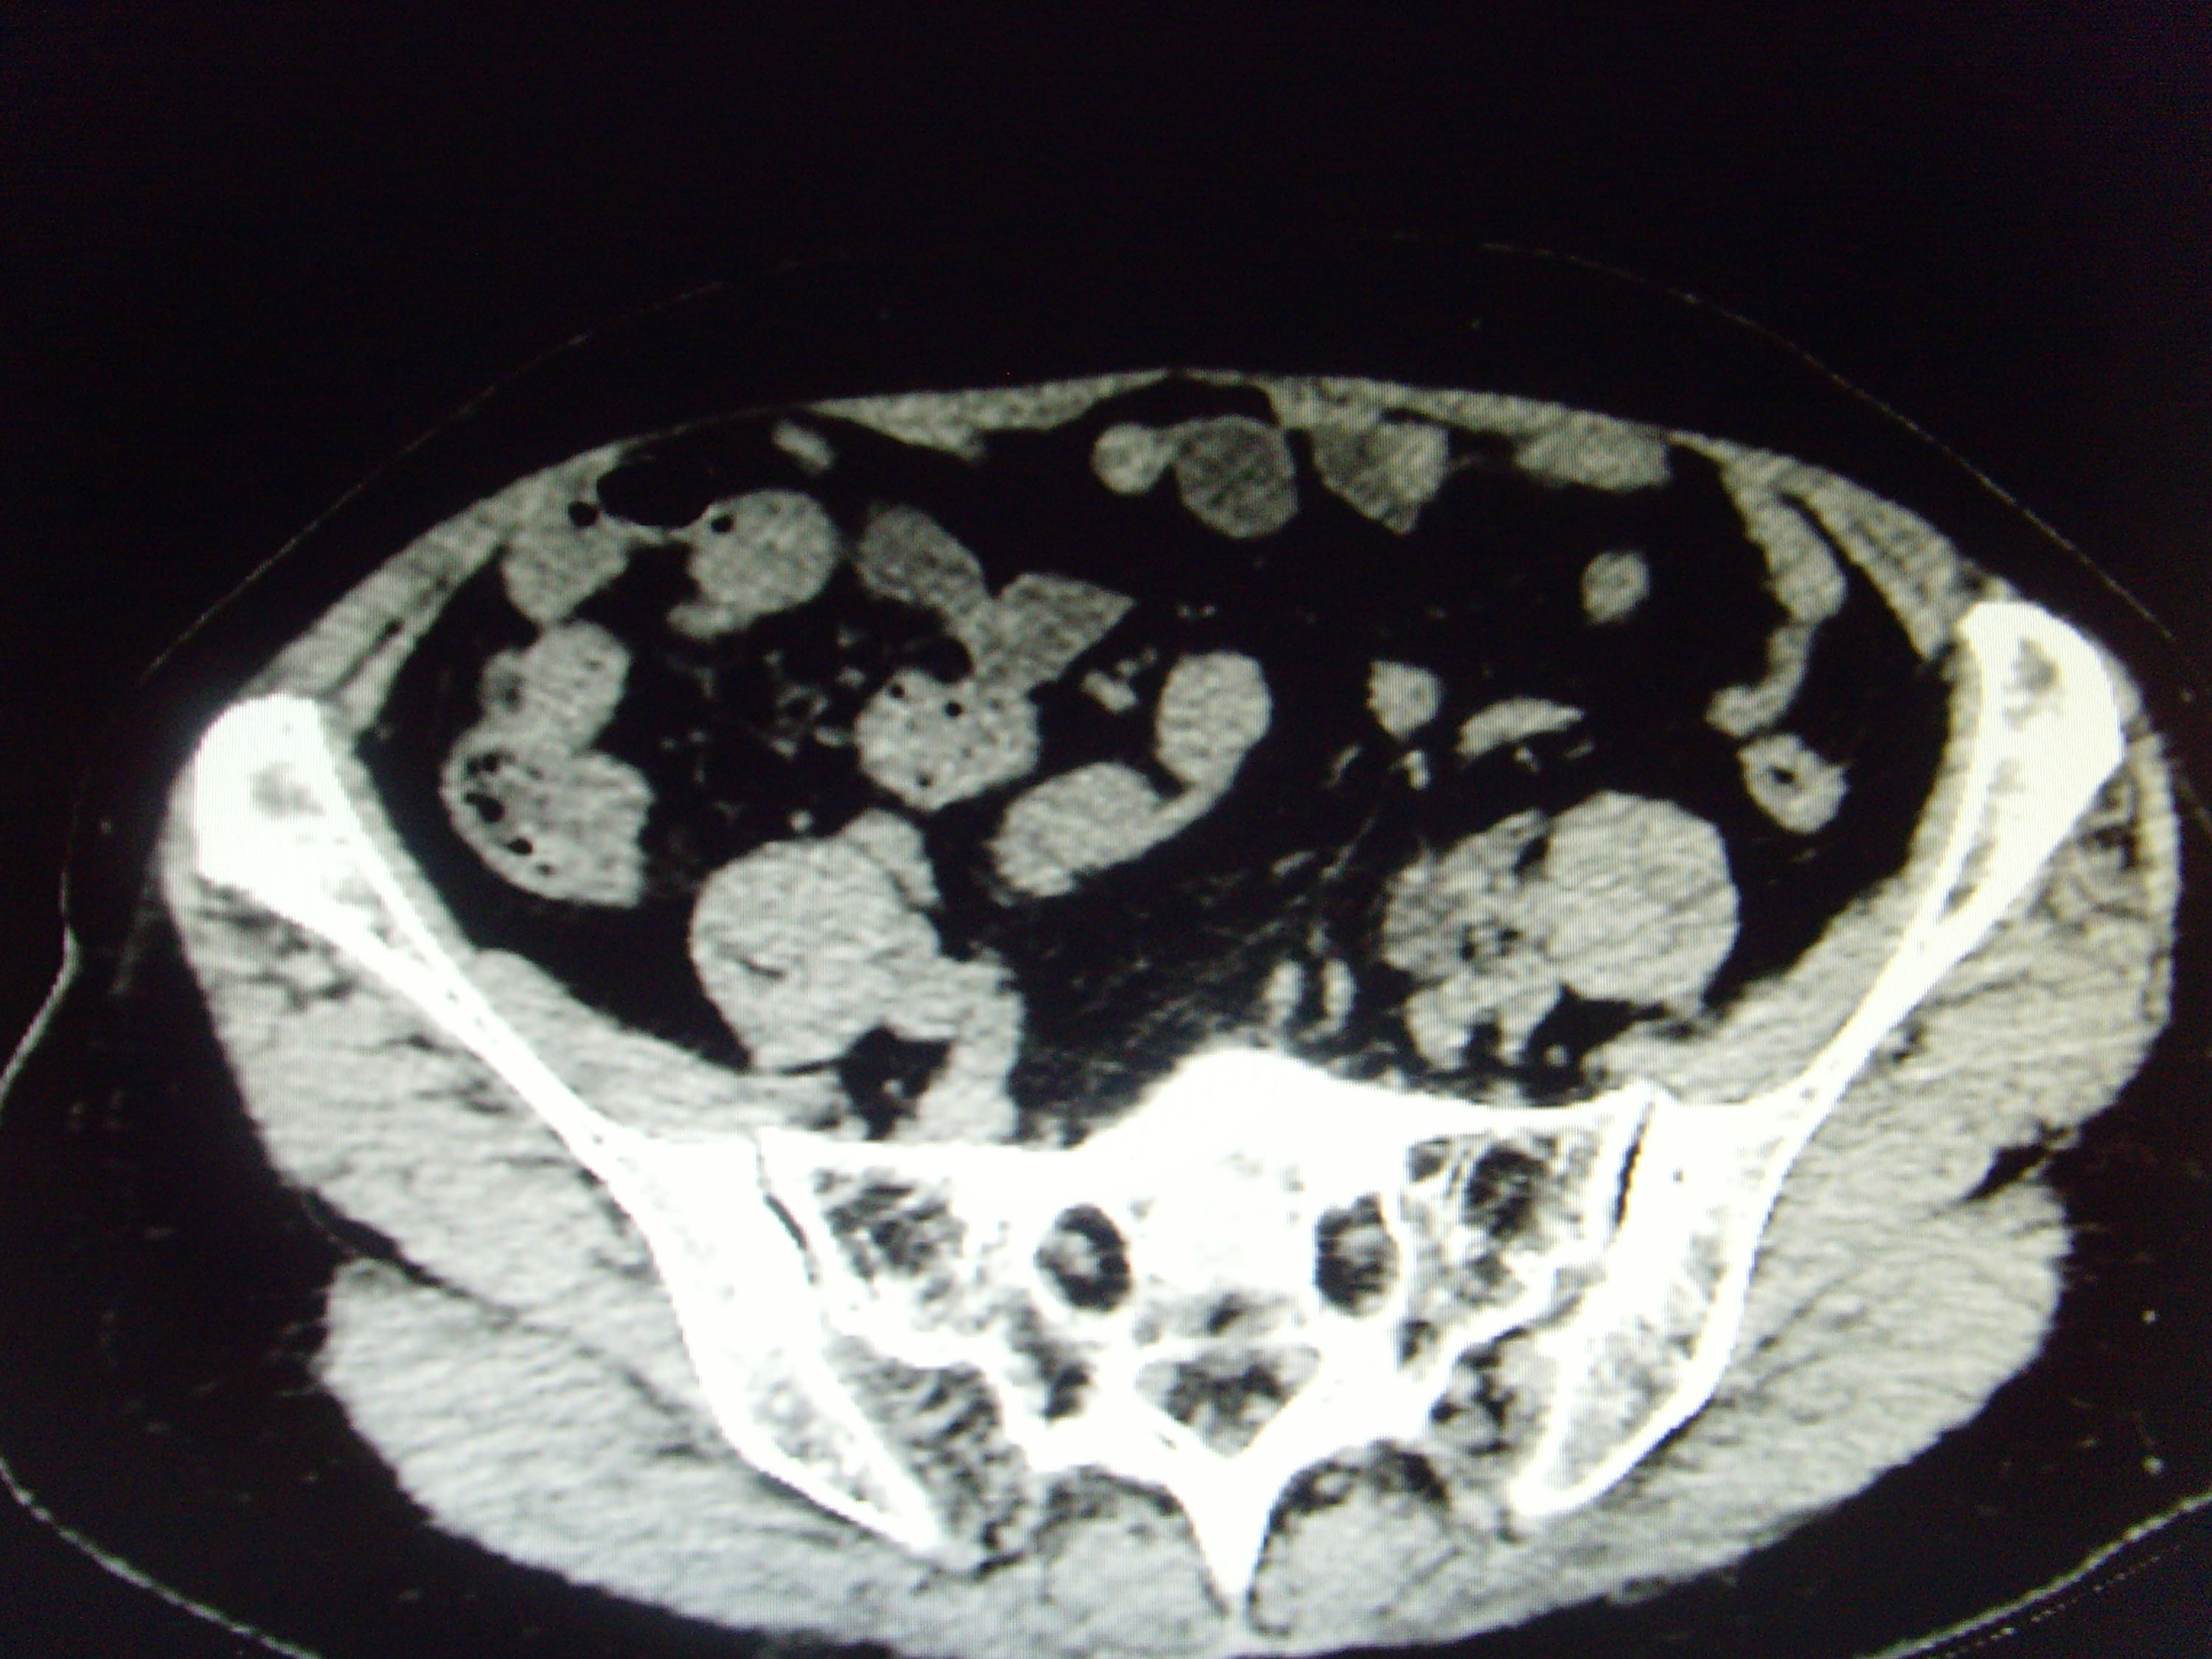

CT51987:盆腔什么病变

女,63岁,盆腔什么病变

左侧附件区可见囊实性占位,以实性为主,肿块与子宫、膀胱分界不清,左侧输尿管下端扩张,考虑:左侧附件区占位-----卵巢癌累及邻近器官可能性大。左侧输尿管下端扩张。

1)考虑左侧卵巢囊腺癌累及邻近结构。2)左侧输尿管下段扩张。

病变呈囊实性,与子宫、左侧附件及膀胱分界欠清,周围似见反应性淋巴结。

1、首先考虑卵巢来源病变,累及 膀胱不除外,建议MR增强扫描。